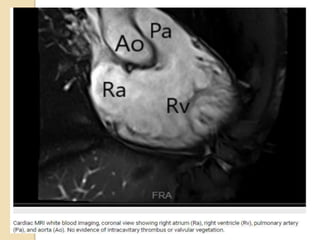

 The coronal plane can be used to

assess the left ventricular outflow

tract, the left atrium, and the

pulmonary veins.

 The axialplane can depict the four chambers of the heart and the pericardium simultaneously.  The sagittal plane can show the great vessels arising in continuity from the ventricles.  The coronal plane can be used to assess the left ventricular outflow tract, the left atrium, and the pulmonary veins.